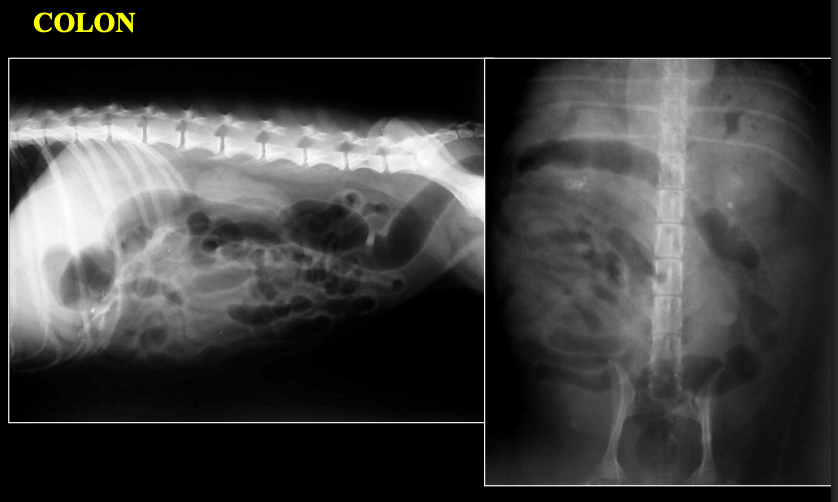

INTESTINO GRUESO – COLON

PERRO: diámetro normal < longitud L7

GATO: diámetro normal < 1,5 × L7

Signo de interrogación en ventrodorsal

MEGACOLON – CONSTIPACIÓN

OTRAS ALTERACIONES

- Engrosamientos: Inflamación, Neoplasia